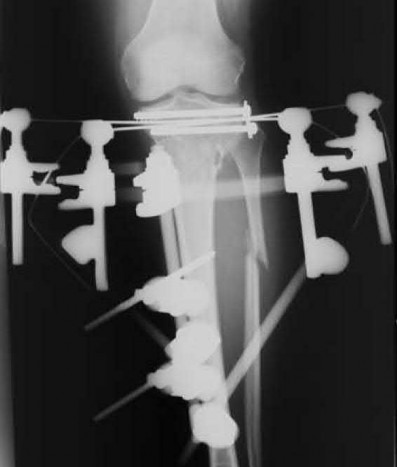

Question 19:

A 28-year-old male sustains a closed comminuted tibial shaft fracture. Two hours post-injury, he develops severe leg pain unyielding to narcotics. His blood pressure is 120/80 mmHg. Intracompartmental pressure monitoring is performed. Based on current guidelines, which measurement dictates an emergent 4-compartment fasciotomy?

Correct Answer: Delta pressure (Diastolic BP - Compartment Pressure) < 30 mmHg

Explanation:

Acute compartment syndrome is classically defined by tissue hypoperfusion. The absolute compartment pressure is less reliable than the differential pressure (Delta P). A Delta P (Diastolic Blood Pressure minus Compartment Pressure) of less than 30 mmHg is an absolute indication for emergency fasciotomy, as capillary perfusion gradient is lost when tissue pressure approaches the diastolic pressure.